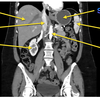

label the arrows on this abdominal CT